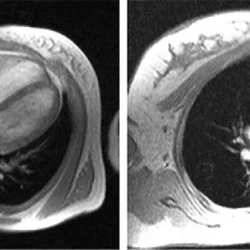

МРТ сердца с контрастированием для диагностики заболеваний и здоровья

Магнитно-резонансная томография сердца: ключ к пониманию здоровья Магнитно-резонансная томография (МРТ) сердца с контрастированием — это...